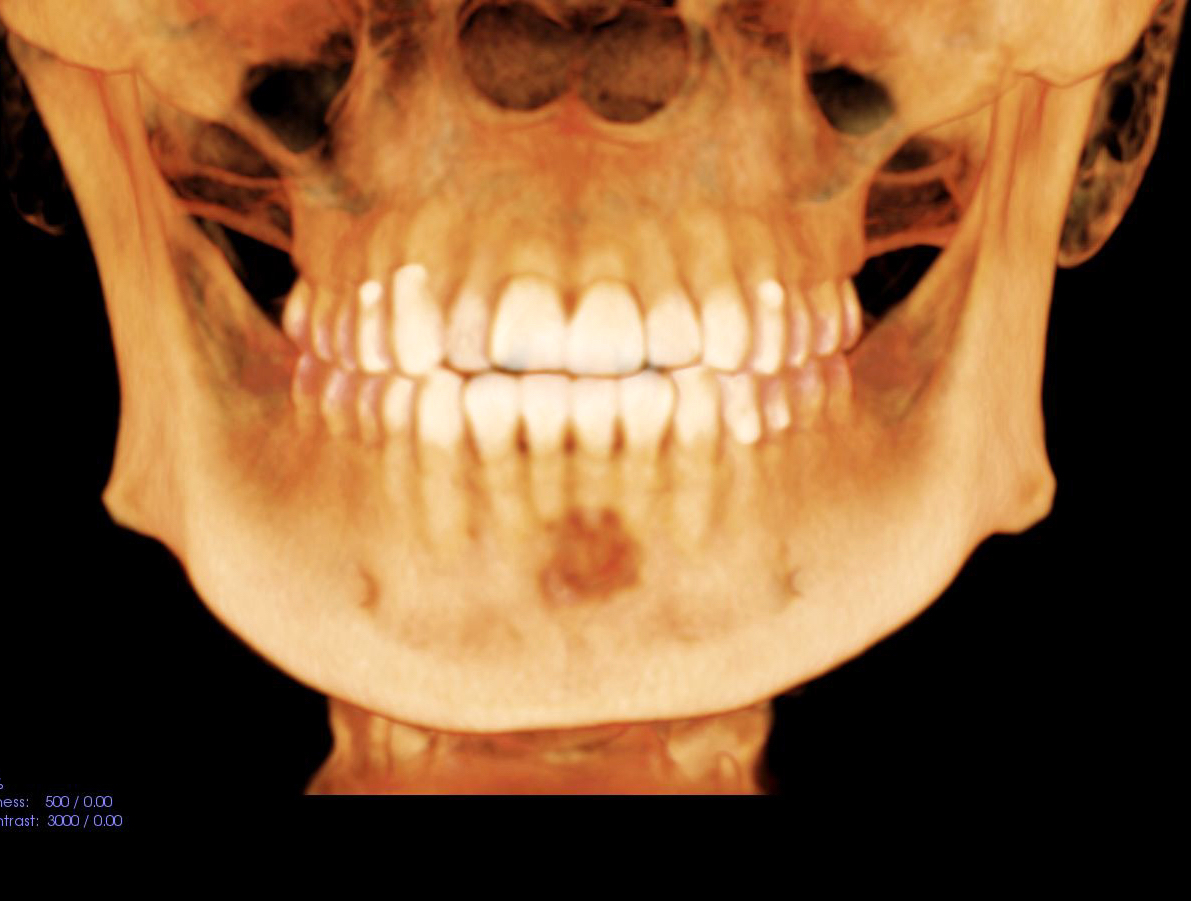

Radiology description

- Radiological findings vary according to maturity of lesion; early lesions show well defined corticated radiolucency and over time, lesion becomes progressively more radiopaque (Heliyon 2021;7:e07594, BMJ Case Rep 2020;13:e239286)

- Well circumscribed, unilocular lesion with centrifugal pattern of growth (Heliyon 2021;7:e07594)

- Can present as lesion with well defined sclerotic borders and is predominantly unilocular (BMJ Case Rep 2020;13:e239286)

- Larger lesions show expansion, thinning and perforation of buccal and lingual cortex and involvement of the lower border of mandible (BMJ Case Rep 2020;13:e239286)

Radiology images